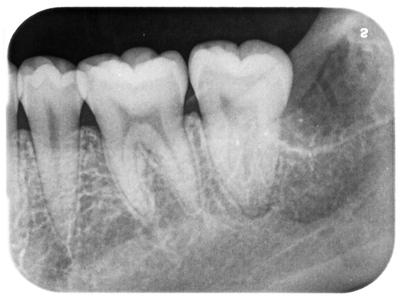

親知らず疼痛で来院。(そもそもは右下親知らず)

前医では抜歯できない、大きな病院を紹介すると言われ、相談に来られた。

問題なく10分位で抜歯完了。

繊細な切開、抜歯を心がけたので、腫れ痛みもほとんどなし。

左下、左上の親知らずも埋伏歯であったが既に当院で抜歯済であり、右上の親知らずは様子見。

難易度は5段階の2程度。

歯周外科処置を多く行っている私には。

前医はこの程度の抜歯も行えず、インプラント云々と言っても説得力ないがこれが現実。